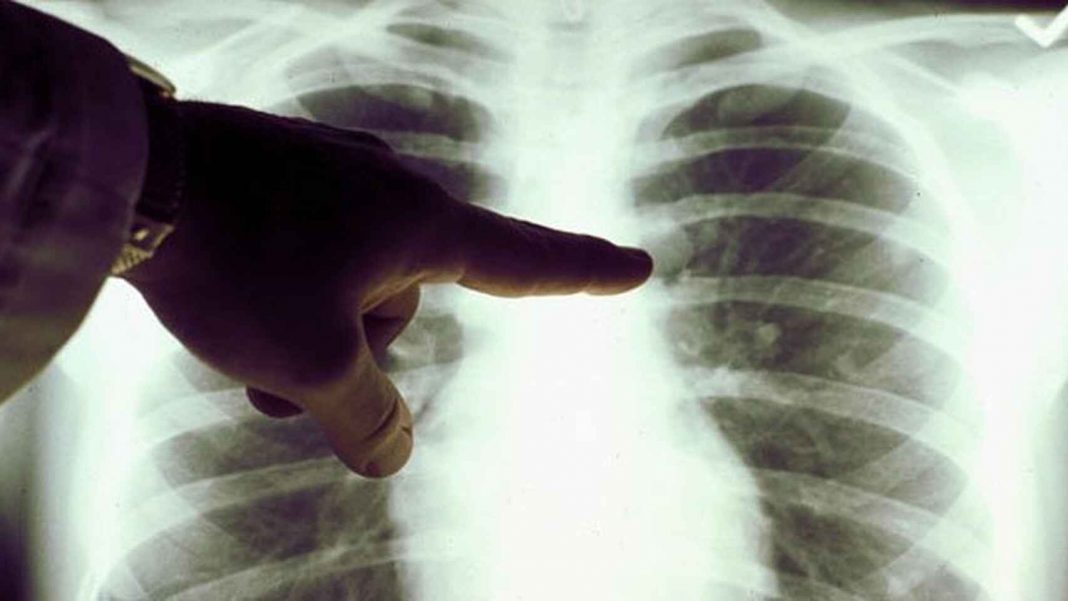

Hay ciertas enfermedades que causan un mayor temor en la sociedad. Este es el caso del cáncer de pulmón. A diferencia de otros padecimientos, este solo causa síntomas cuando ya se ha propagado por gran parte del órgano. Sin embargo, algunas personas con cáncer de pulmón en etapas tempranas presentan síntomas. Por este motivo, en este artículo les contaremos cuáles son los principales síntomas de esta enfermedad. Además, les brindaremos detalles de cómo son los tratamientos y cuál es la esperanza de vida de los pacientes diagnosticados.